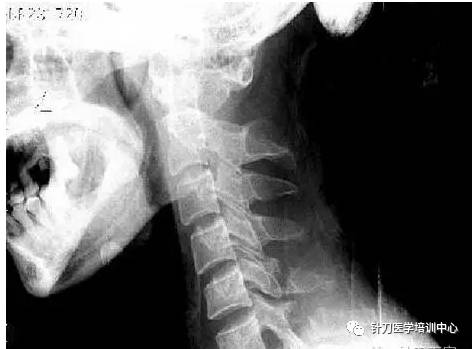

2.根据针刀医学影象诊断学,X线颈椎侧位片示:寰椎后弓与枕骨靠近,加拍颈椎前屈位片,仍显示寰椎后弓与枕骨距离较近。

4)颈椎侧位X片,寰枕后弓和枕骨靠近,如何判断?正常数据是多少?